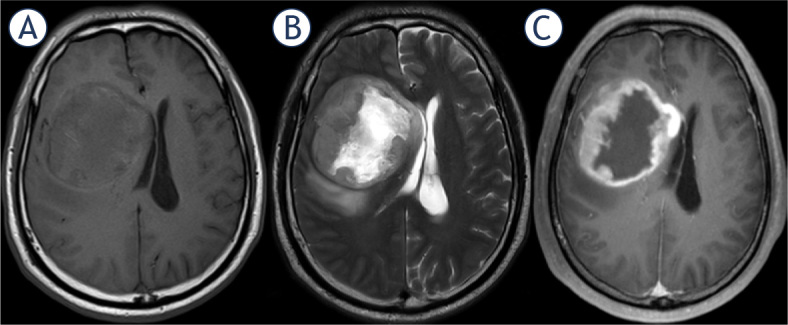

研究背景该研究旨在探讨影像学坏死(Imnecrosis)在胶质瘤分级中的诊断价值,预测胶质瘤的基因型和预后,并通过动态对比增强磁共振灌注成像(DCE-MRI)进一步评估肿瘤坏死:我们回顾性地纳入了150例经病理证实为成人弥漫性胶质瘤的患者(104例男性,平均年龄46岁),所有诊断均基于2021年世界卫生组织(WHO)中枢神经系统(CNS)分类。收集了病理坏死(Panecrosis)和基因突变信息。所有患者均接受了常规和 DCE-MRI 检查,并一直随访至 2021 年 5 月 31 日。Imnecrosis由两名经验丰富的神经放射科医生确定。DCE-MRI得出的指标图经过后处理,记录了肿瘤实质、瘤周和对侧区域每个指标的平均值:在定义瘤体坏死时,观察者之间的一致性很高(Kappa = 0.668,p < 0.001),瘤体坏死和泛坏死之间的一致性也很高(Kappa = 0.767,p < 0.001)。与低级别胶质瘤相比,高级别胶质瘤有更多的Imnecrosis(85.37%,P<0.001),并且Imnecrosis随着胶质瘤级别的增加而显著增加。IDH-野生型、1p19q-非缺码和CDKN2A/B-杂合子缺失胶质瘤中的Imnecrosis明显增多。通过多变量考克斯回归分析,脑坏死是胶质瘤的一个独立且不利的预后因素(危险比=2.113,p=0.046)。此外,DCE-MRI得出的肿瘤实质中血管外细胞外体积分数(ve)在鉴别Panecrosis和Imnecrosis方面显示出最高的诊断效率,特异性很高(分别为83.3%和91.9%):结论:Imnecrosis可为胶质瘤的分级、基因型和预后预测提供Panecrosis之外的补充证据,而肿瘤实质中的ve可帮助预测肿瘤坏死,且特异性高。

Background: The aim of the study was to investigate the diagnostic value of imaging necrosis (Imnecrosis) in grading, predict the genotype and prognosis of gliomas, and further assess tumor necrosis by dynamic contrast-enhanced MR perfusion imaging (DCE-MRI).

Patients and methods: We retrospectively included 150 patients (104 males, mean age: 46 years old) pathologically proved as adult diffuse gliomas and all diagnosis was based on the 2021 WHO central nervous system (CNS) classification. The pathological necrosis (Panecrosis) and gene mutation information were collected. All patients underwent conventional and DCE-MRI examinations and had been followed until May 31, 2021. The Imnecrosis was determined by two experienced neuroradiologists. DCE-MRI derived metric maps have been post-processed, and the mean value of each metric in the tumor parenchyma, peritumoral and contralateral area were recorded.

Results: There was a strong degree of inter-observer agreement in defining Imnecrosis (Kappa = 0.668, p < 0.001) and a strong degree of agreement between Imnecrosis and Panecrosis (Kappa = 0.767, p < 0.001). Compared to low-grade gliomas, high-grade gliomas had more Imnecrosis (85.37%, p < 0.001), and Imnecrosis significantly increased with the grade of gliomas increasing. And Imnecrosis was significantly more identified in IDH-wildtype, 1p19q-non-codeletion, and CDKN2A/B-homozygous-deletion gliomas. Using multivariate Cox regression analysis, Imnecrosis was an independent and unfavorable prognosis factor (Hazard Ratio = 2.113, p = 0.046) in gliomas. Additionally, extravascular extracellular volume fraction (ve) in tumor parenchyma derived from DCE-MRI demonstrated the highest diagnostic efficiency in identifying Panecrosis and Imnecrosis with high specificity (83.3% and 91.9%, respectively).

Conclusions: Imnecrosis can provide supplementary evidence beyond Panecrosis in grading, predicting the genotype and prognosis of gliomas, and ve in tumor parenchyma can help to predict tumor necrosis with high specificity.